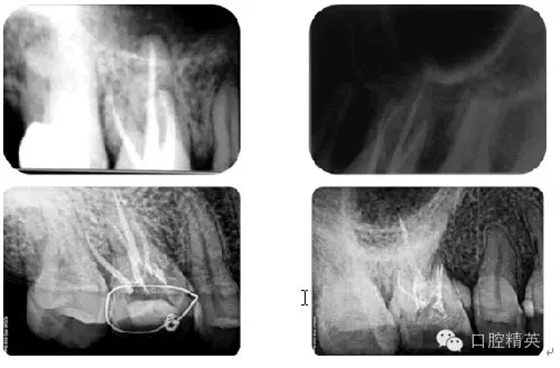

病例2:各型MB2根管

病例4:根管再治療